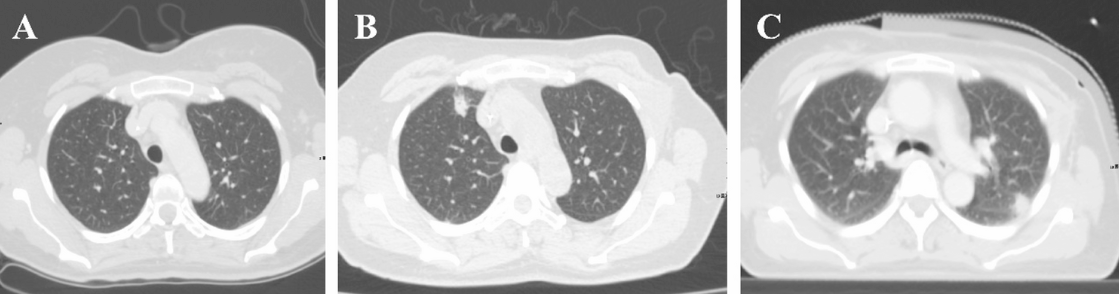

术后初期患者恢复平稳。术后第14天,患者突发高热(Tmax 39.4 °C)伴咳嗽。急查血常规示:白细胞 4.5 × 10^9/L,中性粒细胞 3.19 × 10^9/L;CRP及降钙素原(PCT)均在正常范围。给予双氯芬酸钠对症处理,热势未退。复查胸部CT示双肺多发结节状病变,提示炎症进展(图1A-B)。

出院3周后,因患者依从性差未规律服药,再次因高热入院。复查血培养再次检出新诺卡菌。此外,血清学检测示呼吸道合胞病毒(RSV)IgM抗体水平升高(104.5 AU/mL),结合胸部CT左肺上叶新发结节(图1C),临床考虑由于免疫功能低下导致的新诺卡菌菌血症合并RSV感染。